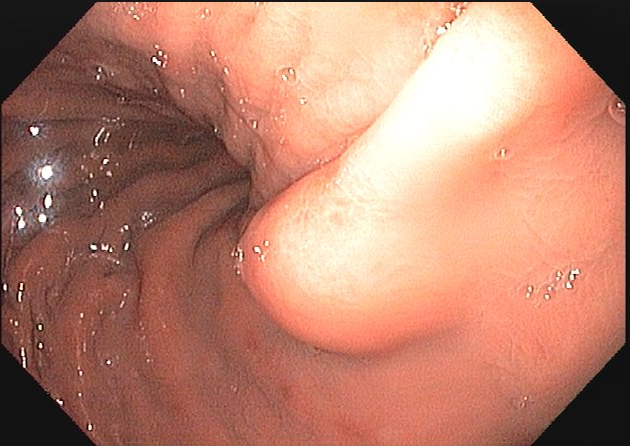

Figuras 1 e 2. Imagem endoscópica em visão direta de lesão protrusa entre pequena curvatura e parede posterior de corpo gástrico proximal, revestida por mucosa com superfície regular, normocorada e íntegra. A imagem ecoendoscópica demonstra lesão com ecogenicidade hipoecoica, ecotextura homogênea, formato ovalado, sem características internas, sem vascularização ao doppler, limites precisos, contornos regulares, medindo aproximadamente 20 x 6 mm e inserida em camada muscular própria. Punções ecoguiadas foram realizadas com agulha FNB, sendo o anatomopatológico e imuno-histoquímica compatíveis com GIST gástrico. Fonte: arquivos do Instituto do Câncer do Estado de São Paulo (ICESP/HCFMUSP)Figuras 1 e 2. Imagem endoscópica em visão direta de lesão protrusa entre pequena curvatura e parede posterior de corpo gástrico proximal, revestida por mucosa com superfície regular, normocorada e íntegra. A imagem ecoendoscópica demonstra lesão com ecogenicidade hipoecoica, ecotextura homogênea, formato ovalado, sem características internas, sem vascularização ao doppler, limites precisos, contornos regulares, medindo aproximadamente 20 x 6 mm e inserida em camada muscular própria. Punções ecoguiadas foram realizadas com agulha FNB, sendo o anatomopatológico e imuno-histoquímica compatíveis com GIST gástrico. Fonte: arquivos do Instituto do Câncer do Estado de São Paulo (ICESP/HCFMUSP)Figuras 3 e 4. Imagem endoscópica em visão direta de abaulamento de parede em segunda porção duodenal distalmente à papila duodenal maior, revestida por mucosa com íntegra, de coloração amarelada e superfície regular. A ecoendoscopia demonstra lesão com ecogenicidade hiperecoica, ecotextura homogênea, formato arredondado, medindo cerca de 10 mm no maior eixo, com limites precisos, contornos regulares, medindo cerca de 10 mm no maior diâmetro e inserida em camada submucosa, sendo os achados endoscópicos e ecoendoscópicos compatíveis com lipoma.Figuras 3 e 4. Imagem endoscópica em visão direta de abaulamento de parede em segunda porção duodenal distalmente à papila duodenal maior, revestida por mucosa com íntegra, de coloração amarelada e superfície regular. A ecoendoscopia demonstra lesão com ecogenicidade hiperecoica, ecotextura homogênea, formato arredondado, medindo cerca de 10 mm no maior eixo, com limites precisos, contornos regulares, medindo cerca de 10 mm no maior diâmetro e inserida em camada submucosa, sendo os achados endoscópicos e ecoendoscópicos compatíveis com lipoma.Fig. 5. Imagem endoscópica em visão direta de lesão protrusa em parede anterior de antro gástrico proximal, revestida por mucosa normocorada, com superfície regular, sendo sugestiva de lesão subepitelial.Fig. 6. A ecoendoscopia evidencia lesão com ecogenicidade hipoecoica, ecotextura predominantemente homogênea, formato arredondado, limites precisos, bordos regulares, medindo aproximadamente 13,4 x 12 mm, sem focos hiperecoicos ou calcificações no interior e inserida na camada muscular própria. Punções ecoguiadas foram realizadas com agulha FNB, sendo anatomopatológico e imuno-histoquímica confirmando schwanomma gástrico.Fig. 7 e 8. Imagem de esofagogastroduodenoscopia demonstra lesão protrusa em papila duodenal maior revestida por mucosa enantemática e com superfície com três erosões recobertas por fibrina.Fig. 7 e 8. Imagem de esofagogastroduodenoscopia demonstra lesão protrusa em papila duodenal maior revestida por mucosa enantemática e com superfície com três erosões recobertas por fibrina.Fig. 9 e 10. Imagem à ecoendoscopia demonstra lesão com formato ovalado, ecogenicidade hipoecoica, ecotextura heterogênea, com contornos regulares, sem adenopatia adjacente, sem vascularização ao doppler, sem características internas, medindo cerca de 20 x 11 x 24 mm, inserida na camada submucosa, não havendo acometimento da muscular própria. Foram realizadas punções ecoguiadas com agulha FNA 22 gauge, sendo o anatomopatológico e imunohistoquímica compatíveis com tumor neuroendócrino de papila duodenal bem diferenciado grau 1.Fig. 9 e 10. Imagem à ecoendoscopia demonstra lesão com formato ovalado, ecogenicidade hipoecoica, ecotextura heterogênea, com contornos regulares, sem adenopatia adjacente, sem vascularização ao doppler, sem características internas, medindo cerca de 20 x 11 x 24 mm, inserida na camada submucosa, não havendo acometimento da muscular própria. Foram realizadas punções ecoguiadas com agulha FNA 22 gauge, sendo o anatomopatológico e imunohistoquímica compatíveis com tumor neuroendócrino de papila duodenal bem diferenciado grau 1.Fig. 11 e 12. Esofagogastroduodenoscopia demonstra abaulamento de parede anterior de corpo gástrico proximal, com mucosa normocorada, superfície regular com depressão central, sendo compatível com lesão subepitelialFig. 11 e 12. Esofagogastroduodenoscopia demonstra abaulamento de parede anterior de corpo gástrico proximal, com mucosa normocorada, superfície regular com depressão central, sendo compatível com lesão subepitelialFig. 13 e 14. Ecoendoscopia demonstrou formação com ecogenicidade hipoecoica, ecotextura homogênea, formato ovalado, limites bem definidos, contornos regulares, medindo aproximadamente 13 mm e inserida na camada submucosa. Lesão foi submetida a ressecção endoscópica transmural com dispositivo FTRD. A histopatologia e imunohistoquímica confirmaram TNE gástrico bem diferenciado grau 2.Fig. 13 e 14. Ecoendoscopia demonstrou formação com ecogenicidade hipoecoica, ecotextura homogênea, formato ovalado, limites bem definidos, contornos regulares, medindo aproximadamente 13 mm e inserida na camada submucosa. Lesão foi submetida a ressecção endoscópica transmural com dispositivo FTRD. A histopatologia e imunohistoquímica confirmaram TNE gástrico bem diferenciado grau 2.